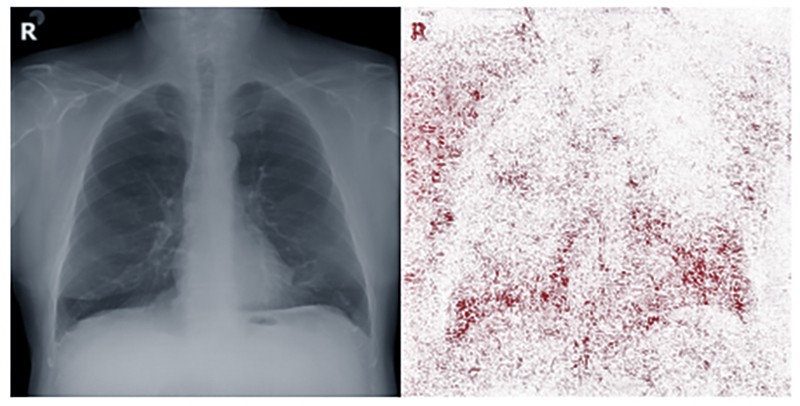

“The Lancet Digital Health” сэтгүүлд бичсэнээр, олон зуун мянган рентген зургийг ашиглан хиймэл оюун ухаан 90 хувийн оновчтой рентген зургаар хүний арьсны өнгийг таньж сурсныг АНУ, Канад, Тайванийн судлаачдын хамтарсан баг тогтоожээ. Ингэхдээ тэд нэг нас, хүйсний хүмүүсийн рентген зургийг ашигласан байна. Хиймэл оюун ухаан хүний арьсны өнгийг хэрхэн тодорхойлж байгааг эрдэмтэд одоогоор хэлж мэдэхгүй байна. Судлаачид зураг дээрх ясны нягтаршил зэрэг санаа өгсөн мэдээллийг арилгасан ч хиймэл оюун ухаан хүний жинхэнэ арьсны өнгийг гайхмаар зөв тодорхойлсоор байжээ. Компьютерын систем арьсны өнгийг ямар байхыг тодорхойлдог меланины одоогоор шинжлэх ухаанд танигдаагүй шинжийг илрүүлж сурсан байж магадгүй гэж эрдэмтэд таамаглаж байна.

Өмнөх судалгаагаар хиймэл оюун ухаанаар рентген зураг уншуулахад хар арьстай өвчтөнүүдийн өвчний шинж тэмдгийг орхигдуулах магадлал өндөр болохыг тогтоосон байна. Тиймээс эрдэмтэд энэ үзэгдлийн учир шалтгааныг тайлахын тулд бүхий л арга хэрэглэн судалж байна. Хиймэл оюун ухаан нь хүний сэтгэх чадварыг дуурайж, мэдээллийн зүй тогтлыг богино хугацаанд тодорхойлдог. Өөрөөр хэлбэл хиймэл оюун ухаан хүний бодол, таамгийг тусгах боломжтой гэсэн үг. Гэвч үүний учир шалтгааныг эрдэмтэд одоогоор тогтоож чадаагүй л байна.